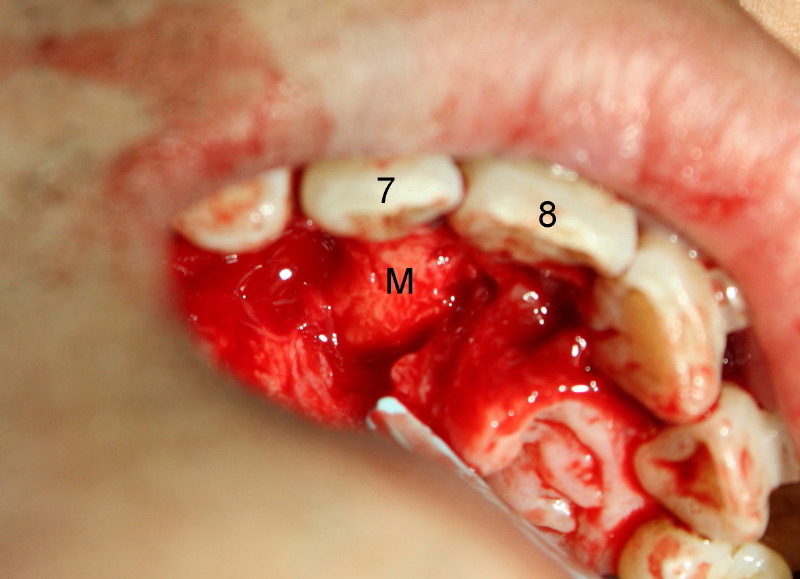

Intraop photos shows the mesiodens (M), palatal to the teeth #7 and 8, after raising palatal mucoperiosteal flap, return to main article